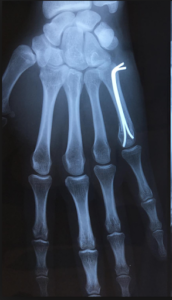

Pour les fractures instables ou déplacées, même si les fragments osseux sont repositionnés et qu’un plâtre est mis en place ensuite, ils auront tendance à re-bouger secondairement ou à adopter une mauvaise position avant de consolider. Ces fractures nécessitent donc une intervention chirurgicale afin de rétablir et maintenir l’alignement des fragments osseux en les fixant avec du matériel qui dépendra du type de fracture (plaque, vis, broches).

Ostéosynthèse par broche, plaque et vis

Lorsque ce sont des broches qui ont permis la réduction du foyer de fracture, ces dernières sont retirées lorsque que le foyer de fracture a consolidé (à 6 semaines en moyenne) au cours d’une seconde intervention au bloc opératoire.

Si des vis ou une plaque ont été posées, il est souhaitable de prévoir leur ablation au cours d‘une nouvelle intervention chirurgicale environ un an après l’accident. Les garder trop longtemps risque d’abimer les tendons. Cette nouvelle opération est à discuter avec votre chirurgien, en fonction de votre âge et/ou de la gêne éventuellement ressentie.